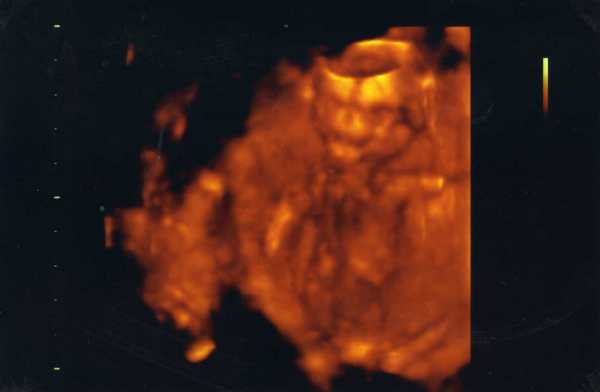

Nagyon szép, formás pocid van!

Nagyon szép a lányod felső teste!

Bár én igazándiból úgy látom, mintha a feje és a lábai is rajta lennének...